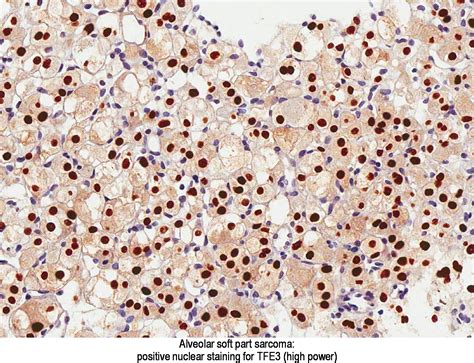

Histopathological examination reveals the characteristic alveolar pattern of ASPS, which is essential for a definitive diagnosis. Additionally, immunohistochemical staining and molecular genetic testing can provide further confirmation.

ASPS is a type of soft tissue sarcoma that originates from the mesenchymal cells, which are responsible for the formation of connective tissues. The disease is named for its distinctive alveolar pattern under the microscope, which resembles the structure of lung alveoli. This pattern is a key diagnostic feature that helps differentiate ASPS from other types of sarcomas.